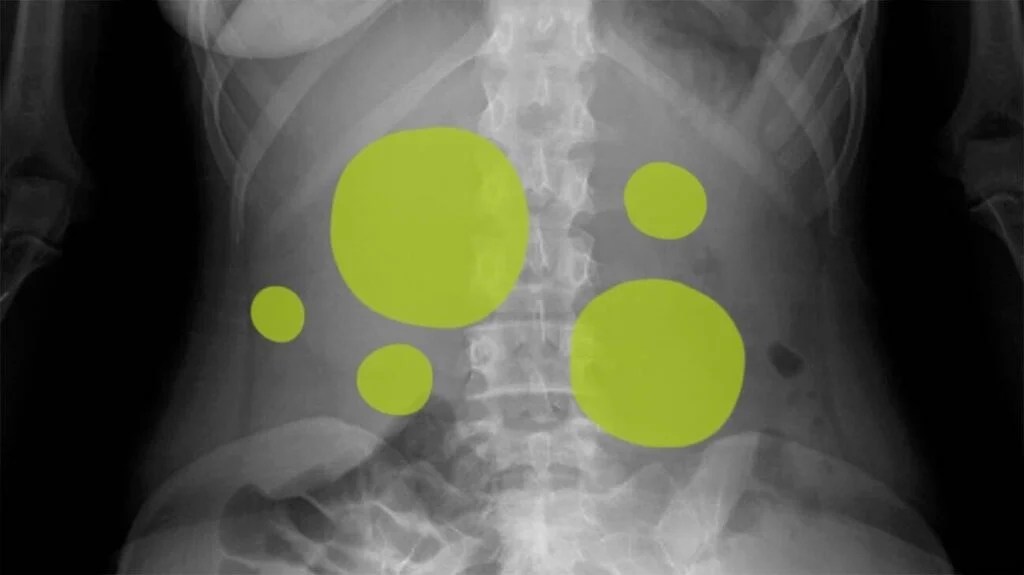

Signs or symptoms of gas or gas pains include. Burping Passing gas Pain cramps or a knotted feeling in your abdomen A feeling of fullness or pressure in your abdomen bloating. Swallowing air from drinking through a straw or chewing. Bloating occurs as a result of gas building up in your stomach and intestines.

I had it once - my stomach was tender bloated thick firm etc. Bloating can cause abdominal pain that ranges from mild to sharp. Bloating is when gas should be passed through flatulence or burping but instead stays in the stomach and intestines. Bloating and gas that does not dissipate could be indicative of serious.

1 Stomach Gas Abdominal bloating can be caused by a range of things such as.